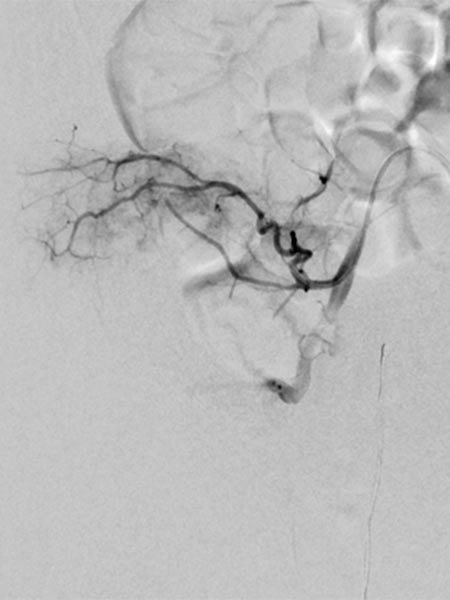

In the final control angiography with long series after injection into the right common iliac artery, the tumor is completely devascularized. The unaffected, physiological arterial branches of the surrounding tissue are all preserved. Thus, the tumor is completely eliminated from the circulation. Activation of coagulation and consumption of platelets in the tumor has stopped.

The typical clinical picture of a newborn with a reddish-bluish tumor immediately after birth, massive coagulopathy with spontaneous hemorrhage and marked thrombocytopenia is clearly indicative of a kaposiform hemangioendothelioma with Kasabach-Merritt phenomenon. In this case, mere substitution of platelets and coagulation factors is usually insufficient. Super-selective embolization while preserving the healthy arteries prevents intratumoral activation of coagulation and trapping of platelets across the massively perfused tumor. This was also very successful in this infant. Currently, the patient is on sirolimus and is developing very well without recurrence.